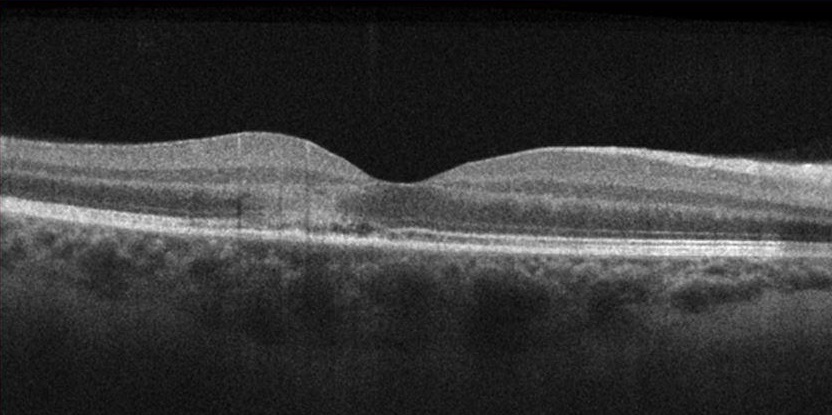

AMN in 22 year old female that presented with bilateral paracentral scotomas and blurry vision. Presenting BCVA was 20/20 OD and 20/25 OS.

Left eye: